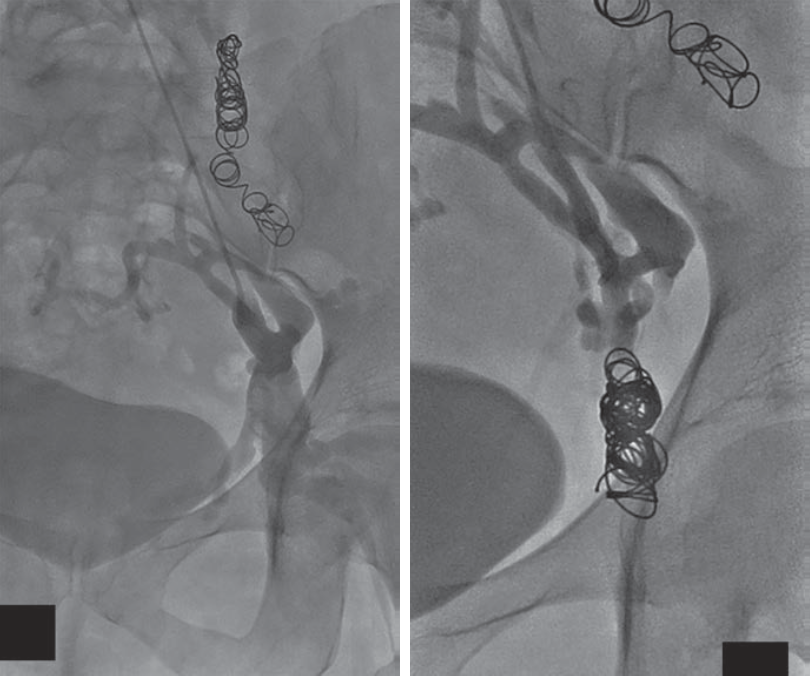

中山经验:“节约型三明治技术”

Sandwich技术优化-节约版

GLUBRAN替代Onxy;

双股静脉入路:可调弯鞘解决反流支;

减少可控圈以及微导管使用;

减少费用;

减少照射;

减少移位;

减少复发;

需解决技术问题:液体栓塞材料溢流。

示例(D-IIV)

示例(LOV+LCV)

节约型三明治技术--中山三板斧